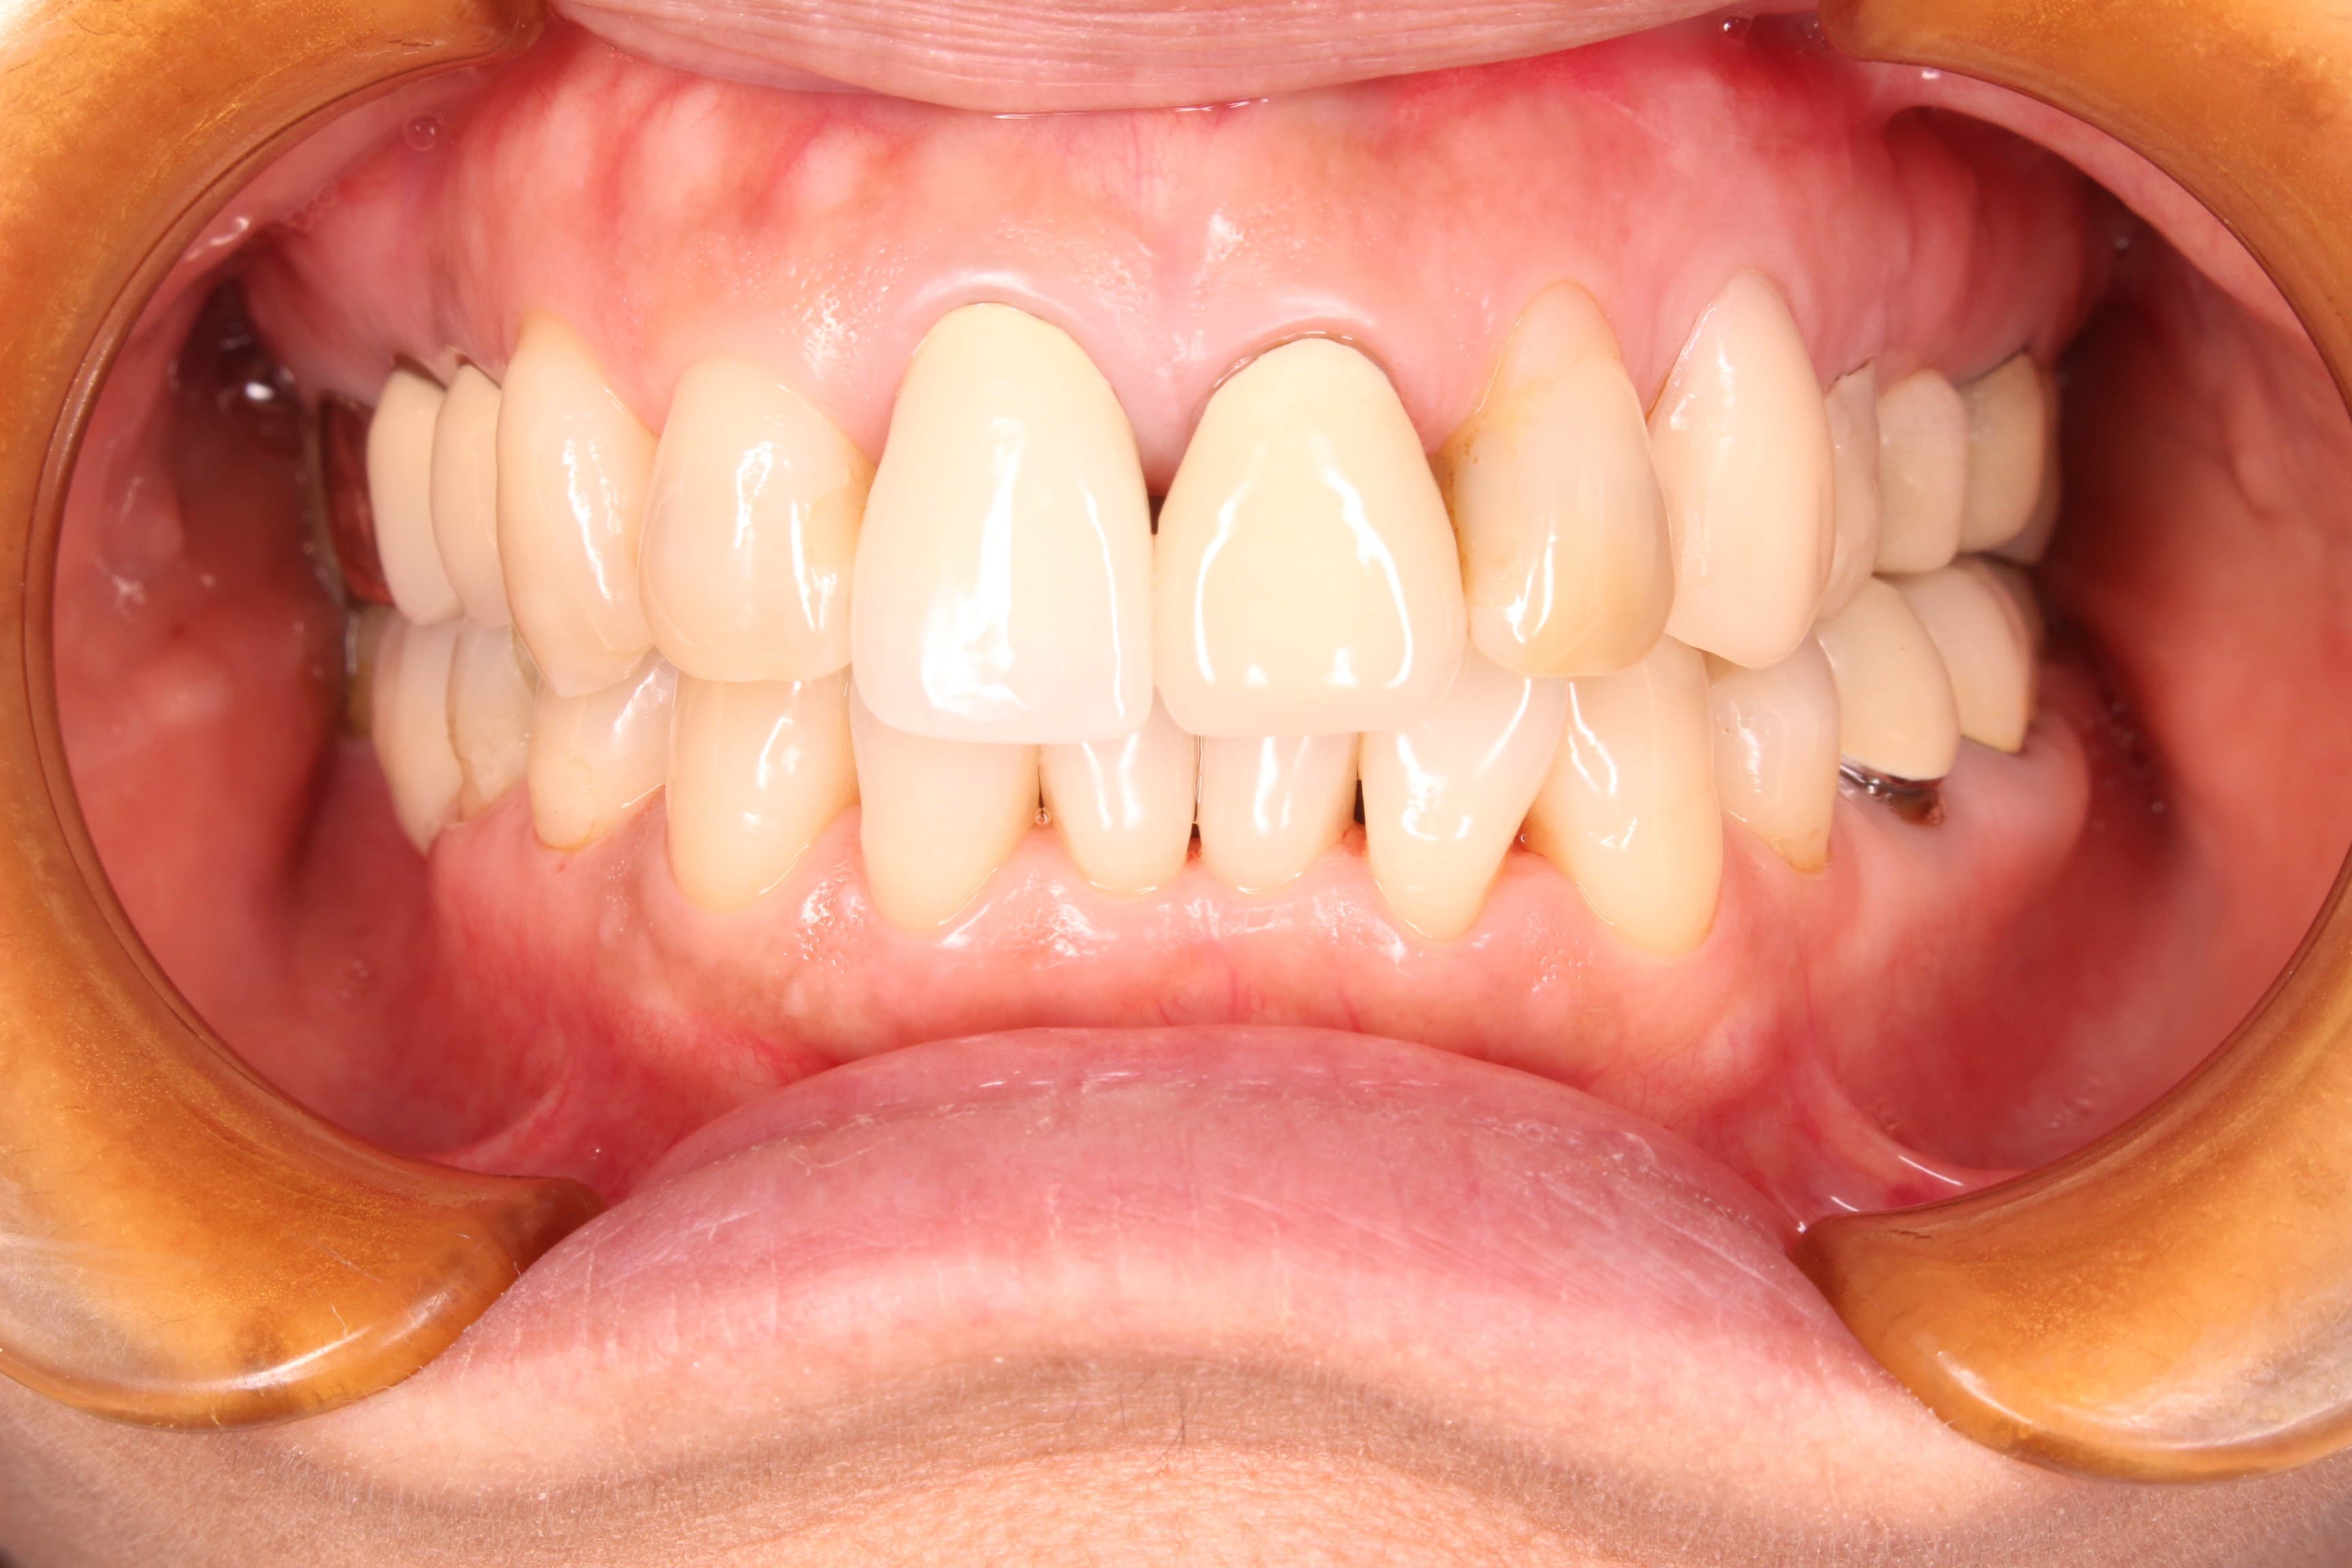

↓治療後

歯周病は、自覚症状は殆どありません。

逆に、自覚症状(グラグラする、膿が出る、腫れあがっている、臭い等)がある場合は、重篤な状態といえるでしょう。

今回の方も、治療する前はなんとも感じていなかったけど、治療後の環境を体感して、以前までは悪い状態だったという事を実感したとのことです。